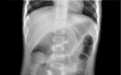

肠套叠的检查目前主要有超声检查和X 线检查两种主要方式,其中X线是目前最主要的诊疗手段,由于不同起病时间的肠套叠在 X 线下可观察到不同的征象。在肠套叠病变早期, 往往不出现气液平面, 由于套叠发生早期肠内气体减少,可见到局限性积气,但此征象不足以诊断肠套叠 。若在结肠中出现一个曲线状肿块( 新月形征) ,特别是在横结肠肝曲后, 以及升结肠内无肠气是影像学上肠套叠的可靠征象 。研究证实空气灌肠时气柱前行过程中形成的“杯口状”团块状影是肠套叠的确诊标准, 具有较高的诊断价值 。腹部X光片的敏感度达到29%~50% 。在多位学者的临床对照实验研究中证实:在多达 25% 的病例中,腹部平片完全正常。因此不建议作为诊断肠套叠首选方法, 但当怀疑有穿孔时, 腹部 X 线片则尤为重要。因常规X线透视对婴幼儿辐射较大,目前已逐渐向低剂量X线透视发展,并取得较好效果。国外等医生通过采用低辐射剂量透视引导下进行空气灌肠复位,成功率高达 95. 8%,与之前的高辐射剂量透视引导下气灌肠复位相比,具有明显的优势。

在关于儿童肠套叠的具体治疗方法上,主要是实施空气灌肠。顾名思义,就是将空气输送到肠道,通过空气压力将套住的肠管归位。在空气灌肠前,一般先给患儿做立/卧位胸腹部平片,排除肺部疾患及膈下游离气体,同时观察疑肠套叠征象。设定复位仪保险压力为 13 kPa,工作压力为 8~13 kPa,最高不超过 15 kPa。由肛门插入球囊导管后进行空气灌肠,注气前在 X 线透视下观察膈下有无游离气体及肠管内气体分布情况,然后缓慢注气,需要在具有透视功能的X线设备下完成操作,目前主要在透视造影胃肠机下完成空气灌肠操作。